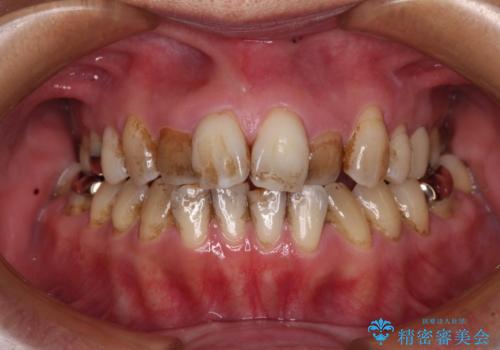

[ インビザライン ] 前歯のガタつきをマウスピース矯正で改善